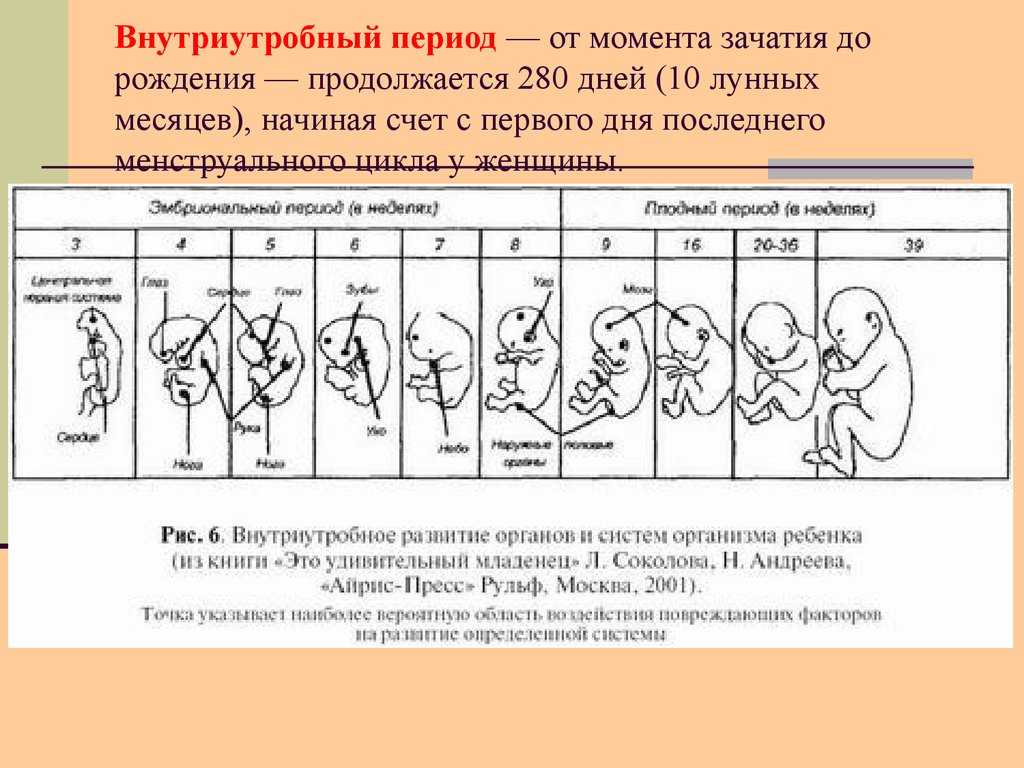

Первые три месяца – это очень важное время и для вас, и для малыша. Он проходит массу преобразований, за считанные дни меняется полностью, закладывается основа всех его органов и систем

Он проходит массу преобразований, за считанные дни меняется полностью, закладывается основа всех его органов и систем. После трех месяцев он начинает вас отчетливо чувствовать, даже реагировать на ваше настроение, звуки, прикосновения – движением.